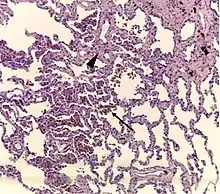

| A "smoker's macrophage", with yellow to light brown and finely granular cytoplasmic pigment. | |

Respiratory bronchiolitis is a lung disease associated with tobacco smoking.[1] In pathology, it is defined by the presence of "smoker's macrophages".[1] When manifesting significant clinical symptoms it is referred to as respiratory bronchiolitis interstitial lung disease (RB-ILD).[1]

- Pathologic: Lung biopsy with "smoker's macrophages" limited to distal airspaces and peribronchiolar airspaces, and minimal to absent peribronchiolar interstitial fibrotic thickening